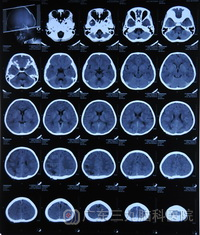

完善相关检查后,2月7日下午,广东三九脑科医院神经外五科主任鲁明利用先进的影像导航设备在全麻下为小虎行“右侧枕叶金属异物取出术”,几经努力,终于探查见一直径约1厘米的有锈迹的圆形钢珠,并成功将钢珠取出。术后小虎康复良好,并将于近日出院。

术前CT 术后CT